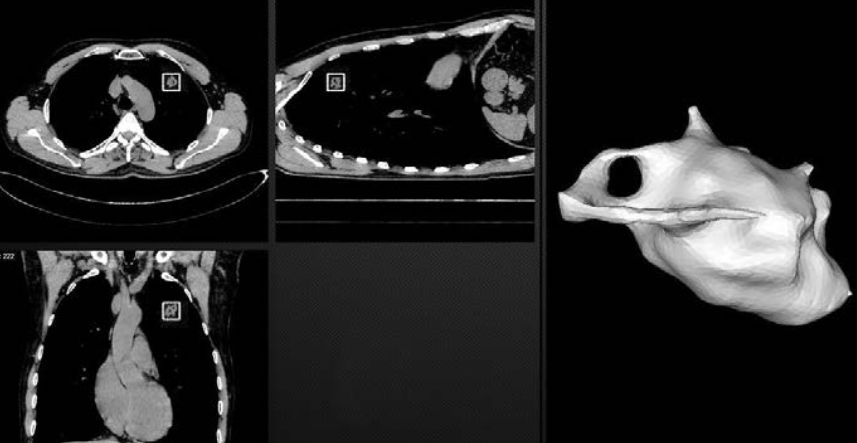

Ученые Политехнического университета совместно с врачами Санкт-Петербургского клинического научно-практического центра специализированных видов медицинской помощи (онкологического) разработали интеллектуальную систему диагностики опухолей в легких. Программное обеспечение, которое можно установить на любом компьютере, за 20 секунд анализирует компьютерную томографию легких пациентов и выдает заключение в виде наглядно выделенной патологии. Разработчики назвали систему Doctor AIzimov (AI – Artificial Intelligence, то есть искусственный интеллект) в честь писателя-фантаста Айзека Азимова, который провозгласил три знаменитых закона робототехники.

В конце 2018 года были проведены закрытые испытания интеллектуальной системы. Она проанализировала анонимизированные снимки компьютерной томографии 60 новых пациентов Онкоцентра. По оценкам врачей, испытания прошли успешно, так как система обнаружила очаговые образования в легких даже малых размеров (2 мм). «Изначально мы настраивали алгоритм на поиск очагов от 6 миллиметров, так как этой тактики придерживаются и сами врачи. Но система настолько обучена, что сама находит новообразования еще меньшего размера», – пояснил Лев УТКИН, руководитель проекта, заведующий Научно-исследовательской лабораторией нейросетевых технологий и искусственного интеллекта.

С каждым новым снимком система сама себя совершенствует. В этом ей помогает суперкомпьютерный центр «Политехнический», который ускоряет настройку алгоритма. Планируется, что снимки пациента по внутренней сети будут отправляться в суперкомпьютерный центр Политеха, где их обработка займет уже не 20, а две секунды, после чего врач получит размеченное изображение и будет работать уже с ним, а не с объемной компьютерной томографией – это сокращает время анализа.